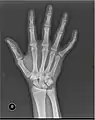

X-ray

X-ray image of right hand with thumb on left.

X-ray image of human infant left hand.